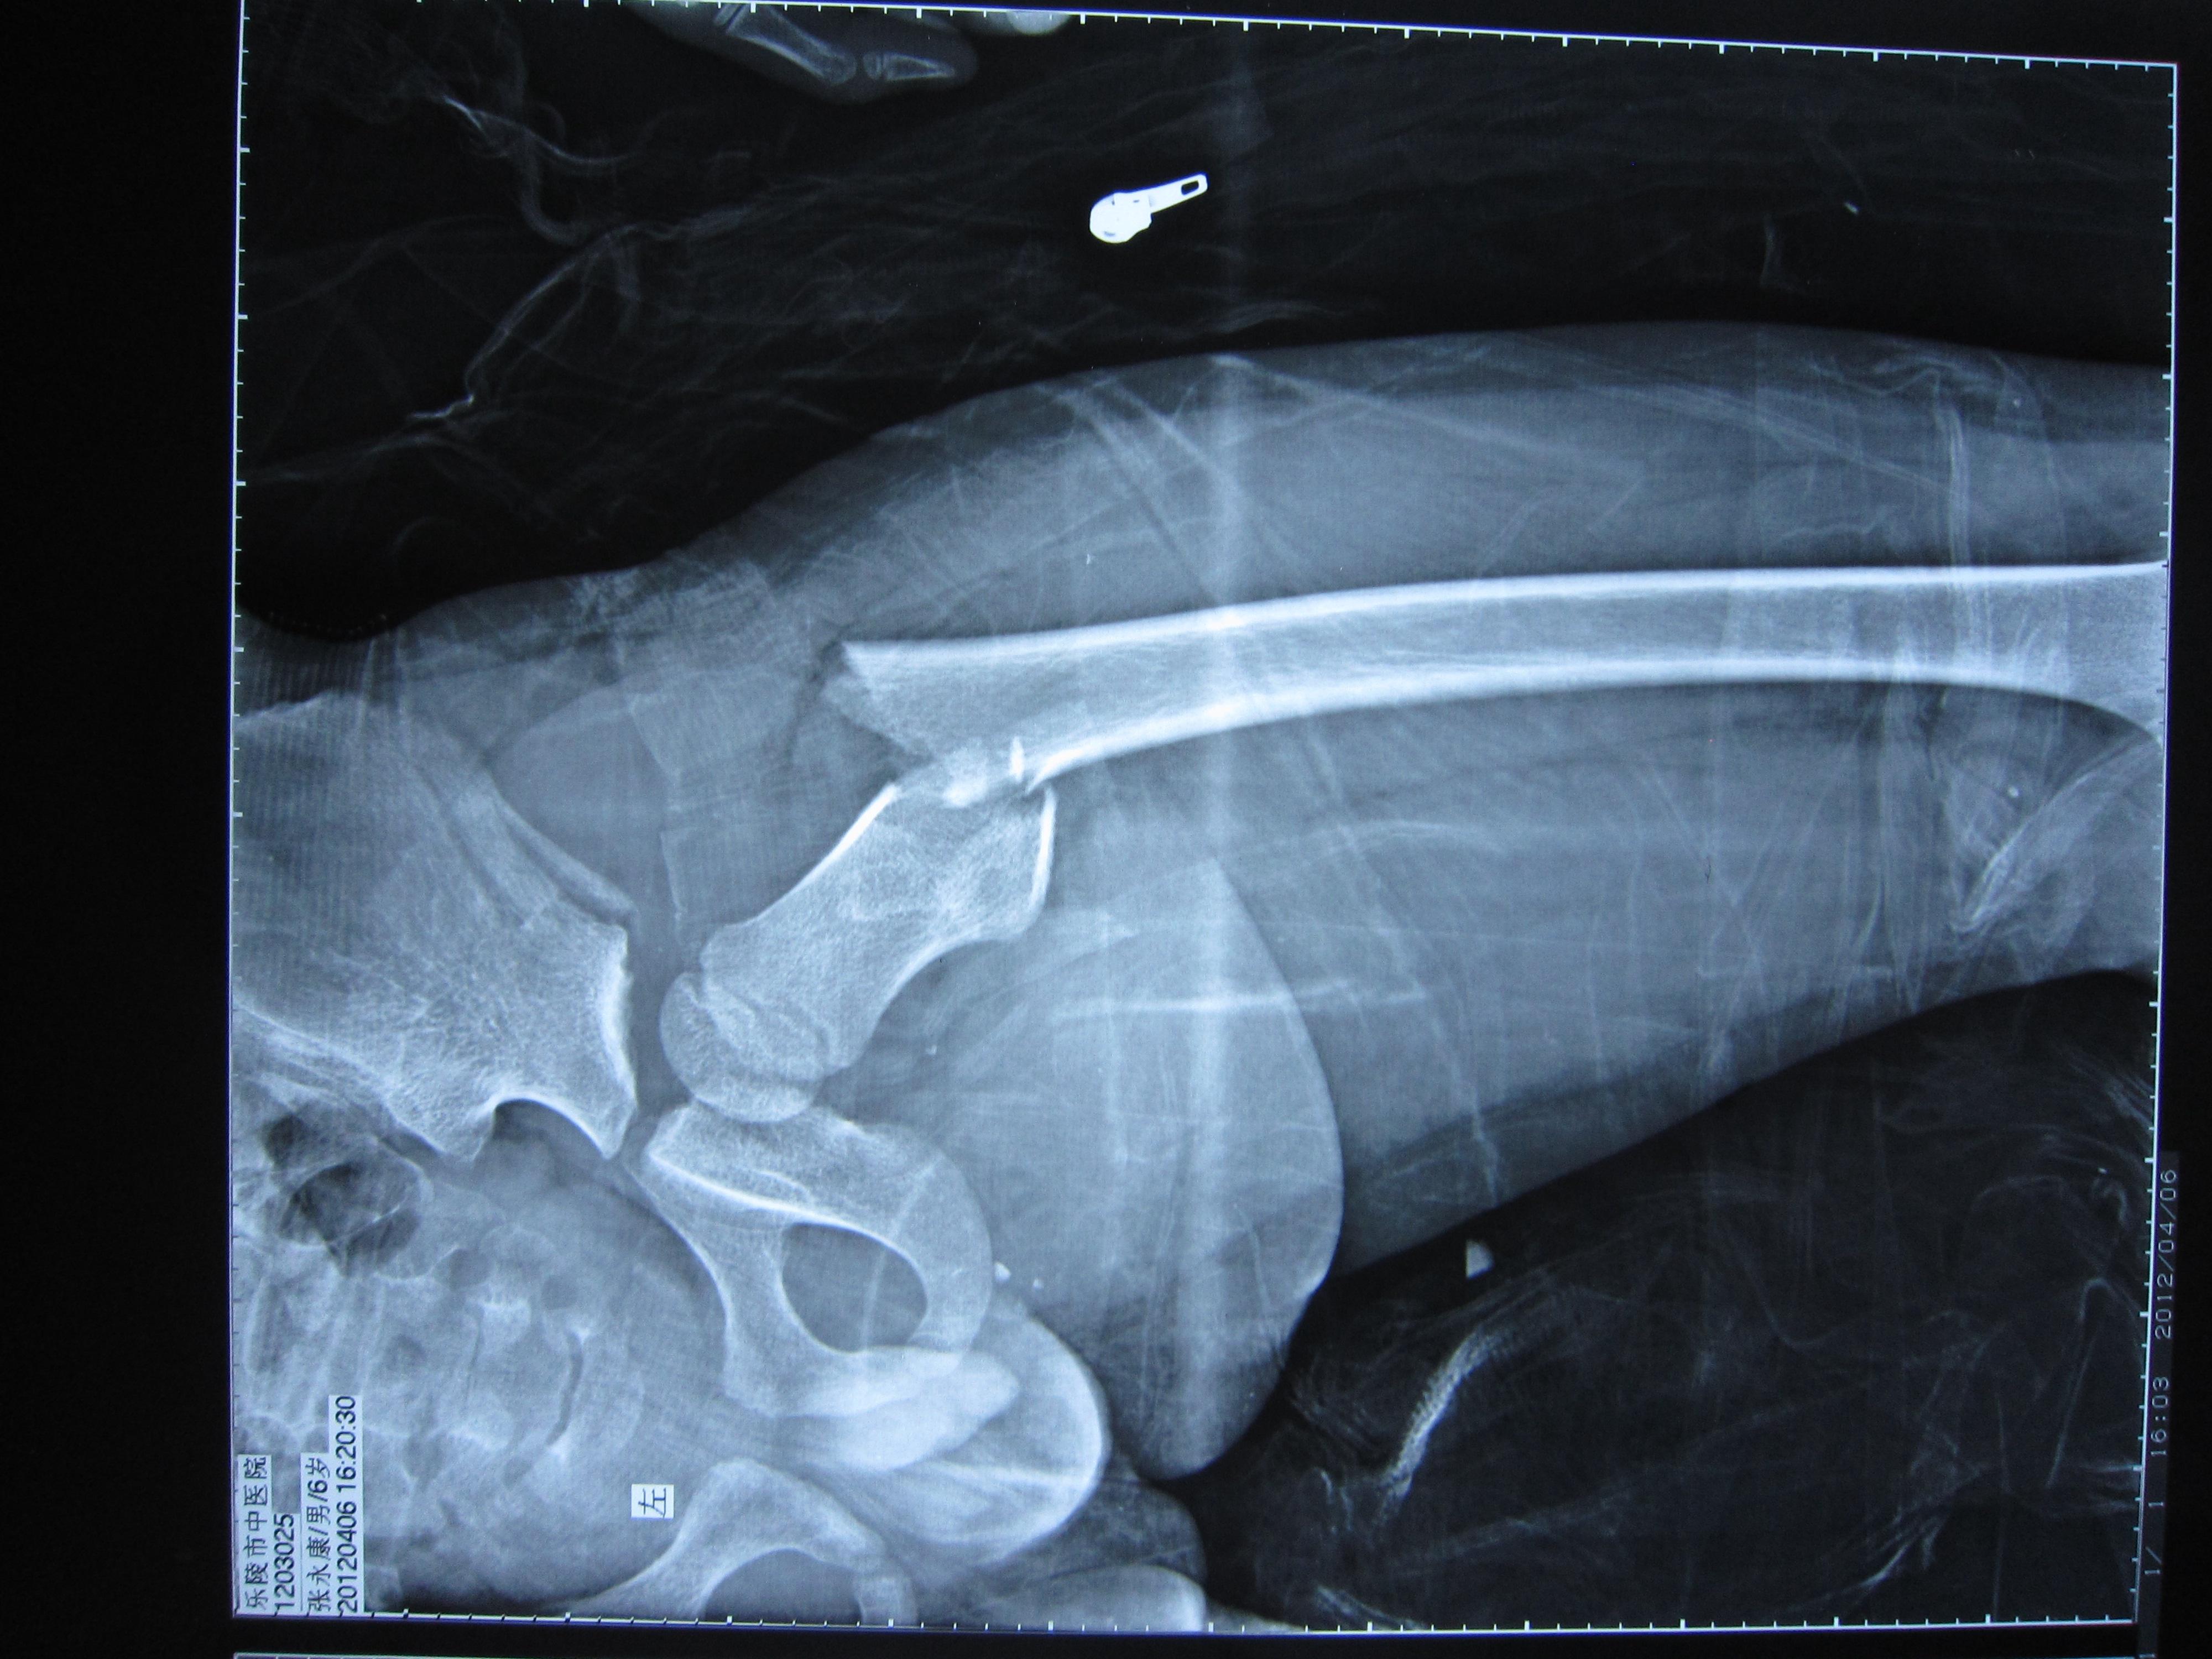

转子下骨折

图片尺寸1080x2280